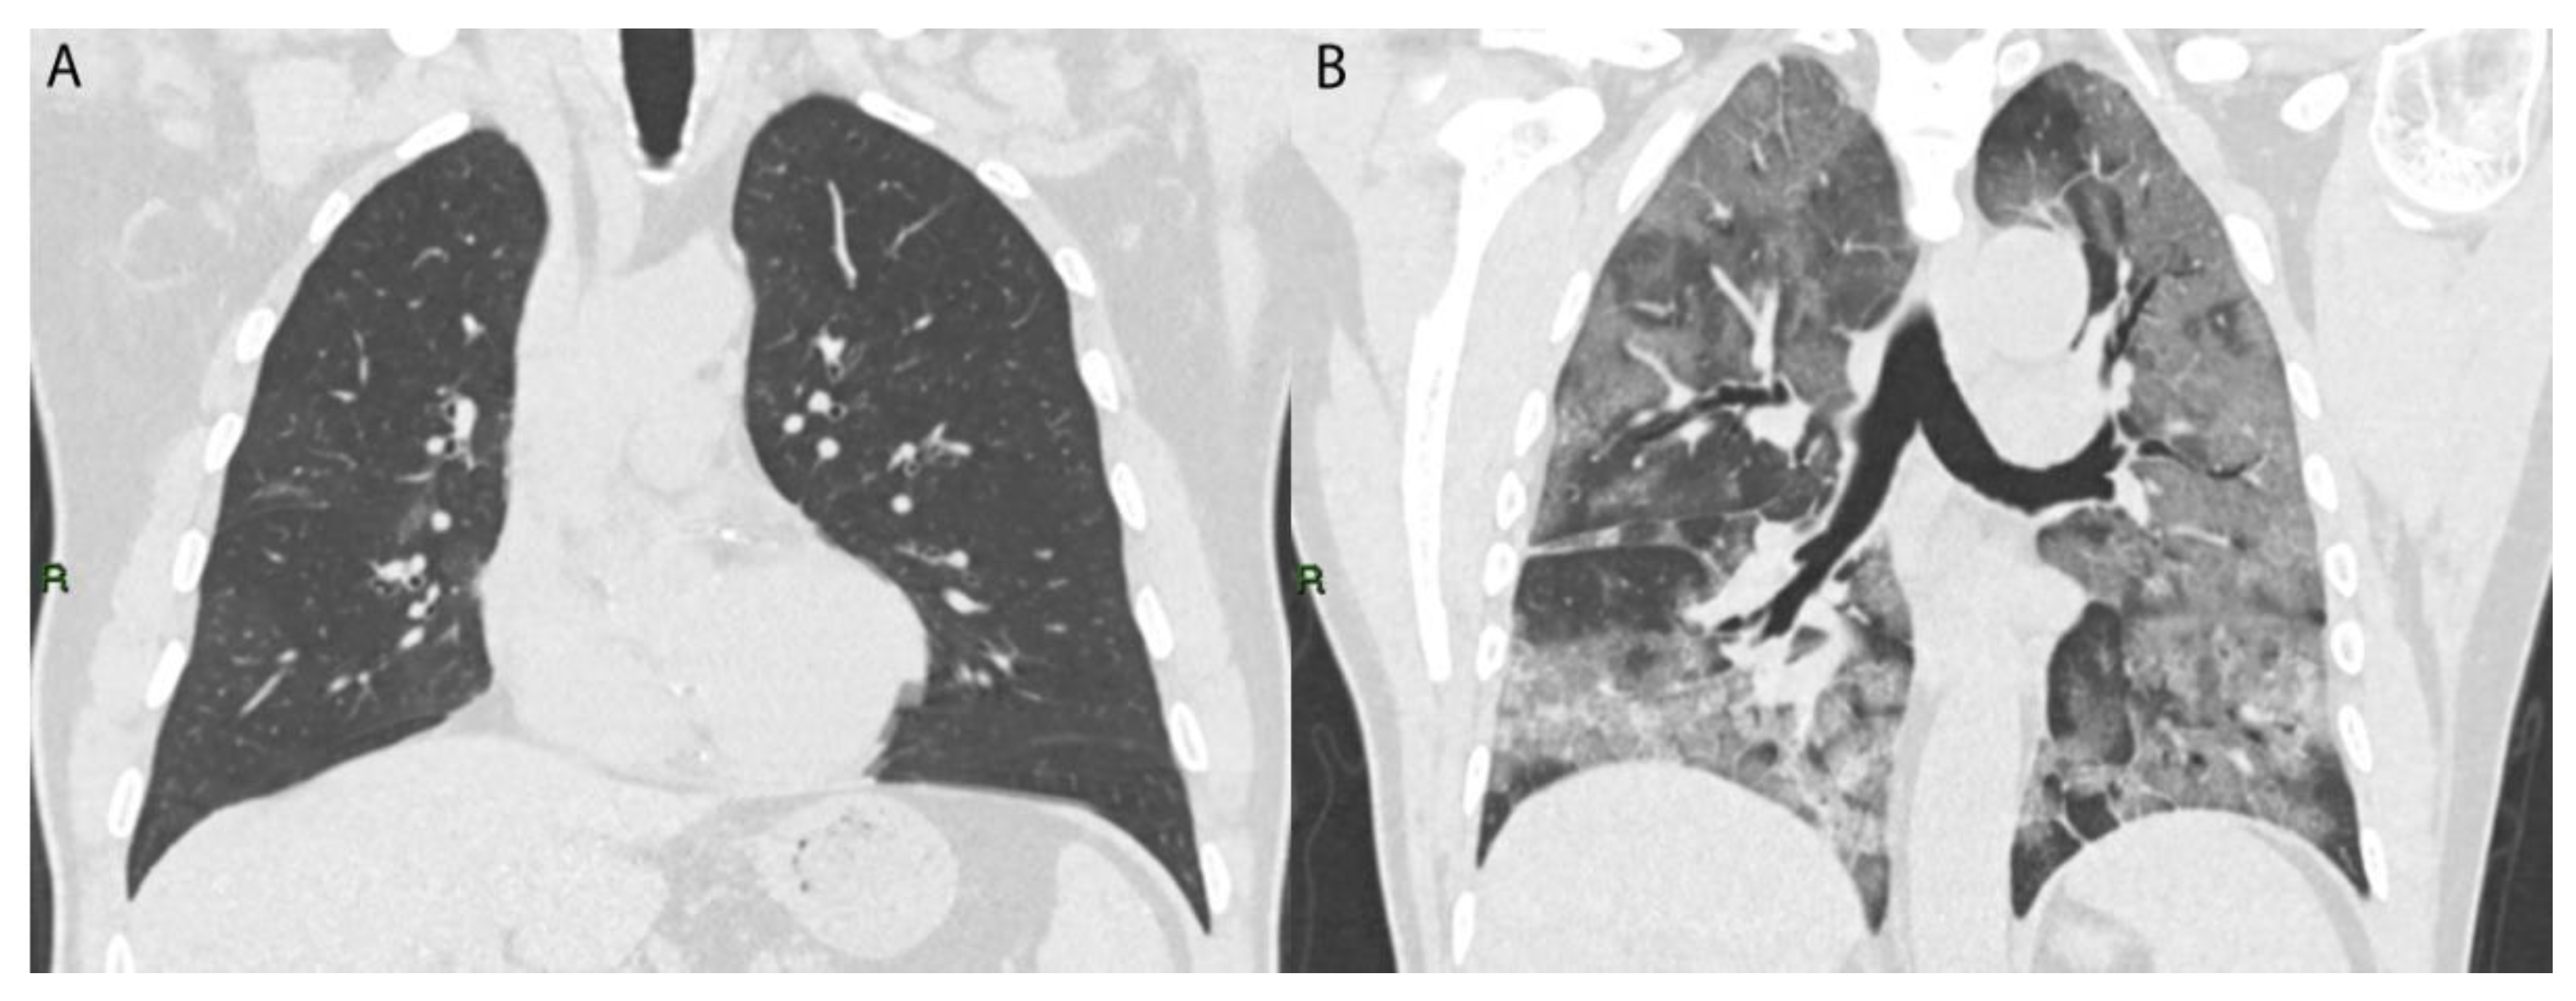

To estimate the involvement of lung lesions, we used a semi-quantitative CT-score system that ranged from 0 to 5 points for each lobe (Figure 4).

Figure 4. Coronal TC image of two COVID-19 patients: (A) patient with low CT score (5/25); (B) patient with high CT score (24/25).